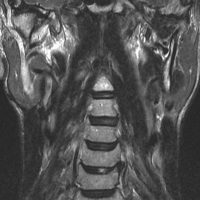

脊髄根 spinal rootから発生した無症候性の副神経鞘腫です。神経根は脊髄前根からでて脊髄の外側から背側へと上行するので,脊髄を横から圧迫するようになります。

徐々に増大しました。手術摘出を行うときに副神経を温存できないと,胸鎖乳突筋と僧帽筋の麻痺が生じます。